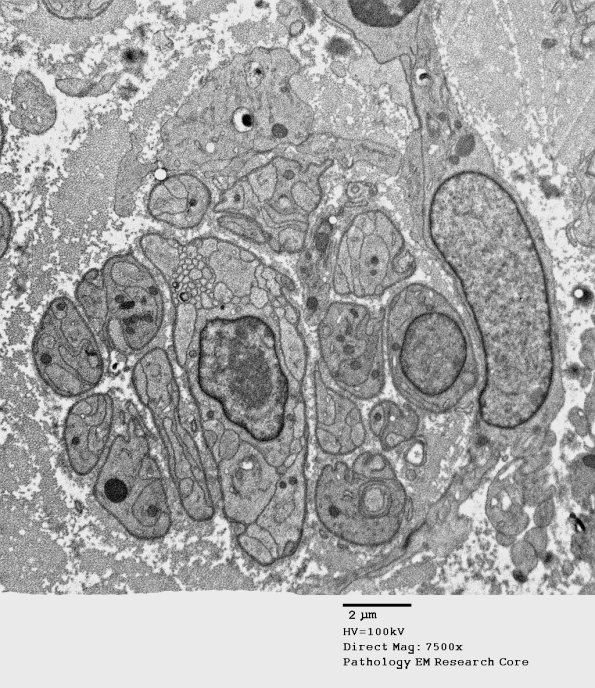

2F1-3 Schwann cells form bands of Büngner once axons degenerate. (electron micrographs)